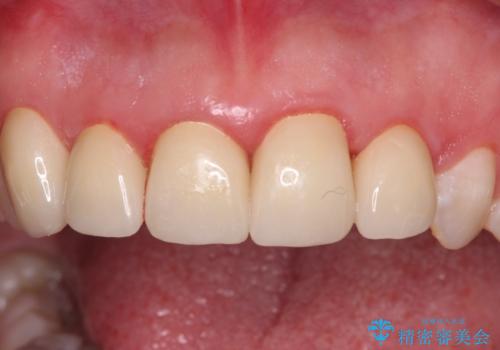

金属の裏打ちを用いたセラミッククラウンであったため歯肉縁に黒ずみが見えてくることは良くありますが、全体的に歯列が不揃いであることが気になったので、それらをオールセラミッククラウンにて改善することとしました。

オールセラミッククラウン装着後、レントゲン写真より精度良く装着されていることは確認できているので、日頃のブラッシングで改善させるよう指導しています。